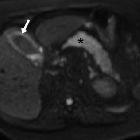

Diffusion-weighted

MRI: findings and role in acute cholecystitis. Apparent diffusion coefficient map showed hypointensity indicating restricted diffusion in gallbladder wall (arrow, 1.45-1.6x10-3 mm2/s) and pancreas (*, progressively increasing from 0.8 at head to 1.1x10-3 mm2/s in tail).